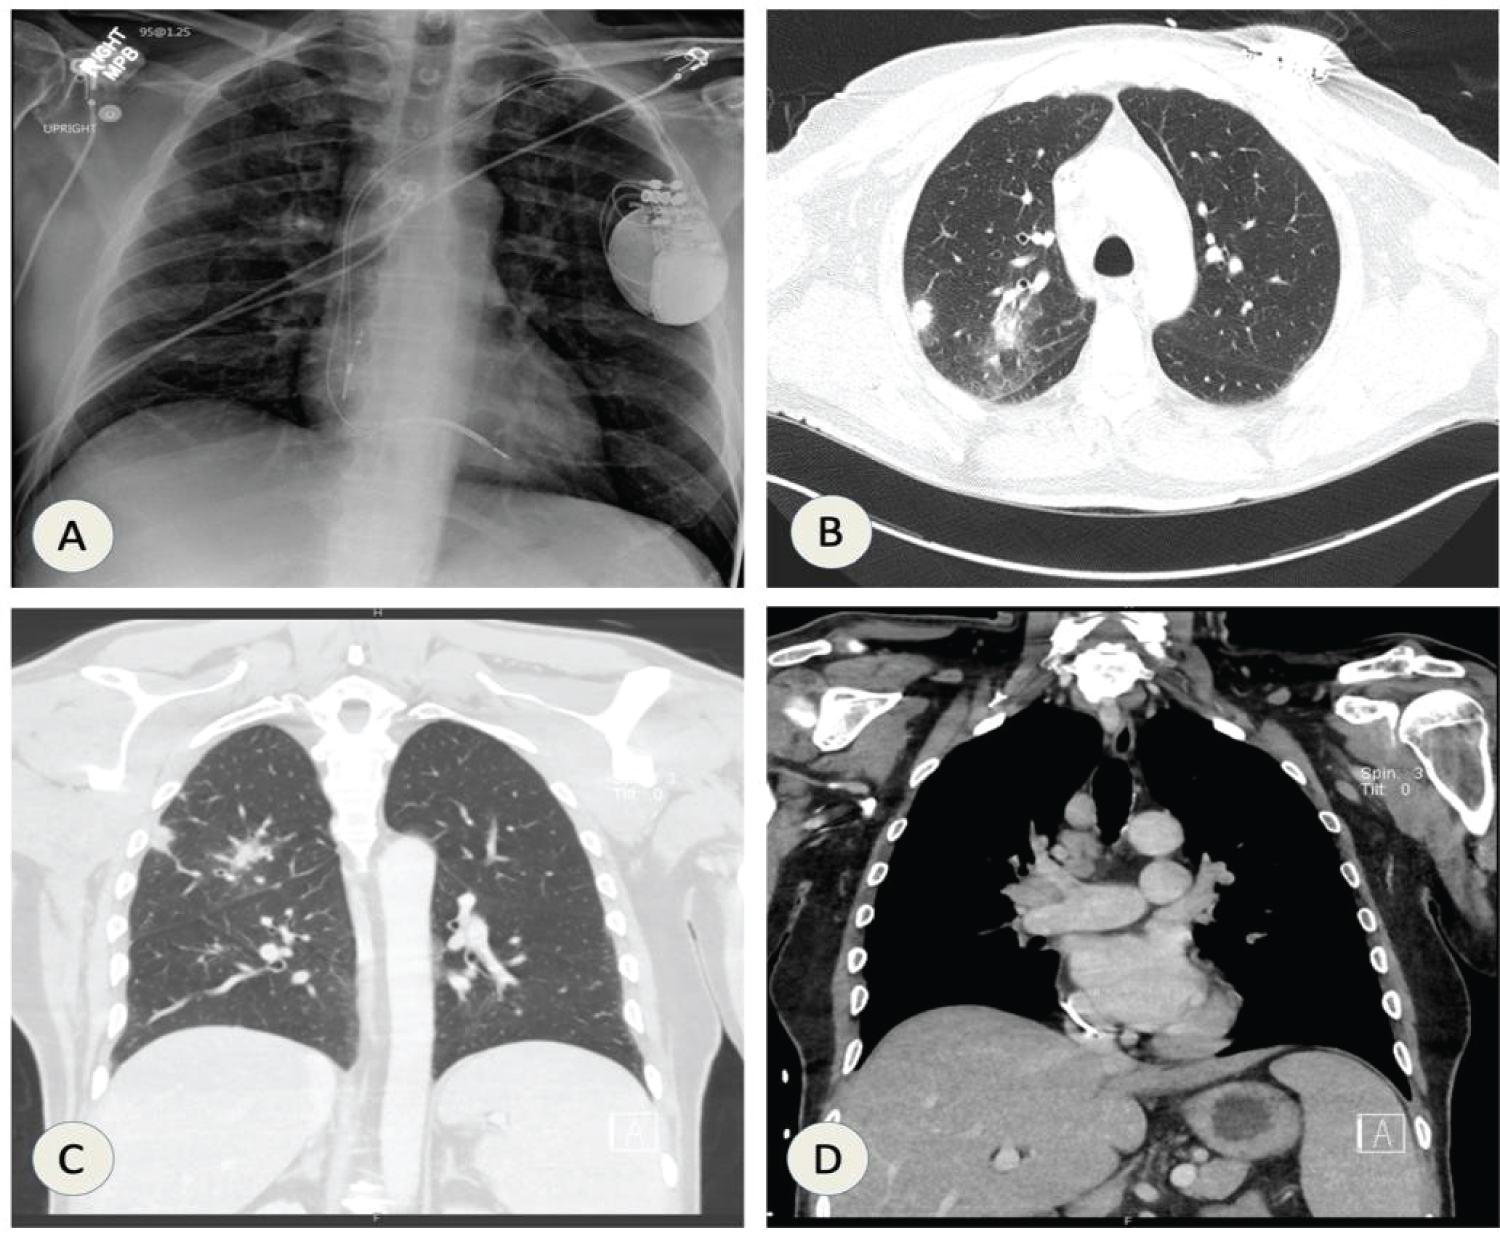

During this admission, CXR was suggestive of consolidation in the right middle lobe as shown in Figure 8A.

Patient was started on ceftriaxone and azithromycin but he continued to spike high-grade fevers despite being on antibiotics. Non-contrast CT scan of chest was done which was suggestive of consolidation in right middle lobe with central areas of necrosis along with mediastinal lymphadenopathy (Figure 8B and Figure 8C).

Figure 8: (A) CXR showing right middle lobe consolidation; (B & C) CT chest showing right middle lobe consolidation along with mediastinal lymphadenopathy. View Figure 8

A 64-year-old male with an extensive smoking history (69 pack-year), chronic obstructive pulmonary disease (COPD), nonischemic cardiomyopathy with implantable cardioverter-defibrillator (ICD), and type 2 diabetes presented with complaints of having nonproductive cough, night chills and unintentional weight loss for the past few weeks. Chest X-ray was suggestive of 12 mm smooth density along lateral aspect of right upper lobe as shown in Figure 10A. CT chest showed right upper lobe parenchymal masses with bulky mediastinal and right hilar lymphadenopathy as shown in Figure 10B, Figure 10C and Figure 10D.

Figure 10: (A) CXR shows 12 mm small rounded density seen along the lateral aspect of the right upper lobe inferior to the posterior aspect of the right fourth rib; CT chest (B & C) showing right peripheral upper lobe mass; (D) Mediastinal and right hilar lymphadenopathy. View Figure 10